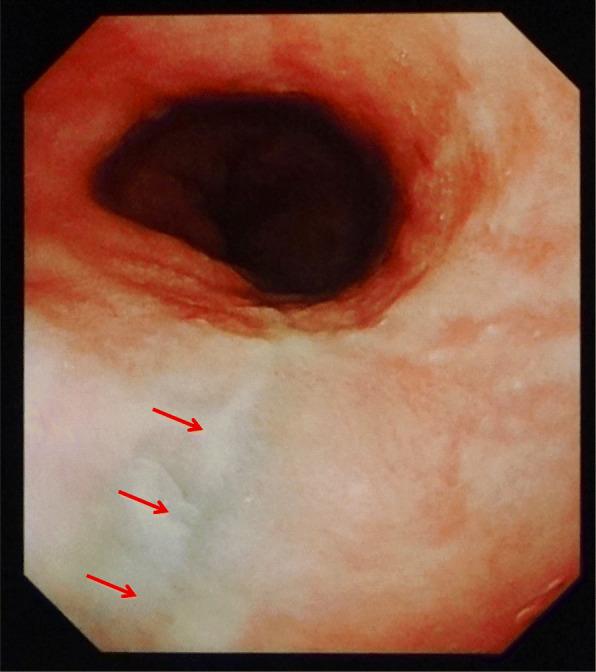

The patient in case 1 complained of severe chest pain and nausea and vomited on arrival at the hospital. He was subsequently diagnosed with Boerhaave syndrome coupled with mediastinitis using computed tomography (CT) and esophagogram. An emergency operation was successfully performed, in which a 3-cm tear was found on the left posterior wall of the distal esophagus. The patient subsequently had anastomotic leakage but was discharged 41 days later. The patient in case 2 complained of severe chest pain, nausea, vomiting, and hematemesis on arrival. He was suggested of having Boerhaave syndrome without mediastinitis on CT. The symptoms gradually disappeared after conservative treatment. Upper gastrointestinal endoscopy performed on the ninth day revealed a scar on the left wall of the distal esophagus. The patient was discharged 11 days later. In addition to the varying severity between the cases, the patient in case 2 was initially considered to have Mallory-Weiss syndrome.

病例1中的患者在入院时主诉严重胸痛、恶心并呕吐。随后通过计算机断层扫描(CT)和食管造影被诊断为Boerhaave综合征合并纵隔炎。成功进行了急诊手术,术中发现食管远端后壁有一处3厘米的撕裂口。该患者随后出现吻合口漏,但在41天后出院。病例2中的患者在入院时主诉严重胸痛、恶心、呕吐和呕血。CT检查提示其患有Boerhaave综合征但无纵隔炎。保守治疗后症状逐渐消失。在第9天进行的上消化道内镜检查显示食管远端左壁有一处瘢痕。该患者在11天后出院。除了病例之间严重程度不同外,病例2中的患者最初被认为患有马洛里-魏斯综合征。